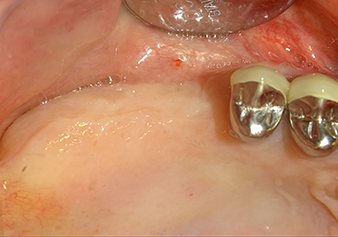

To move the augmentation material in the direction of the maxillary sinus atraumatically, the implant was inserted very slowly by hand (Fig. 9). In the process, the membrane was pushed in the cranial direction once again. After two months, the surgical site healed without irritation. Six months later, the x-ray check showed a significant increase in opacity as an indication of ossification (Fig. 10). The prosthetic restoration was carried out with a metal-ceramic crown.